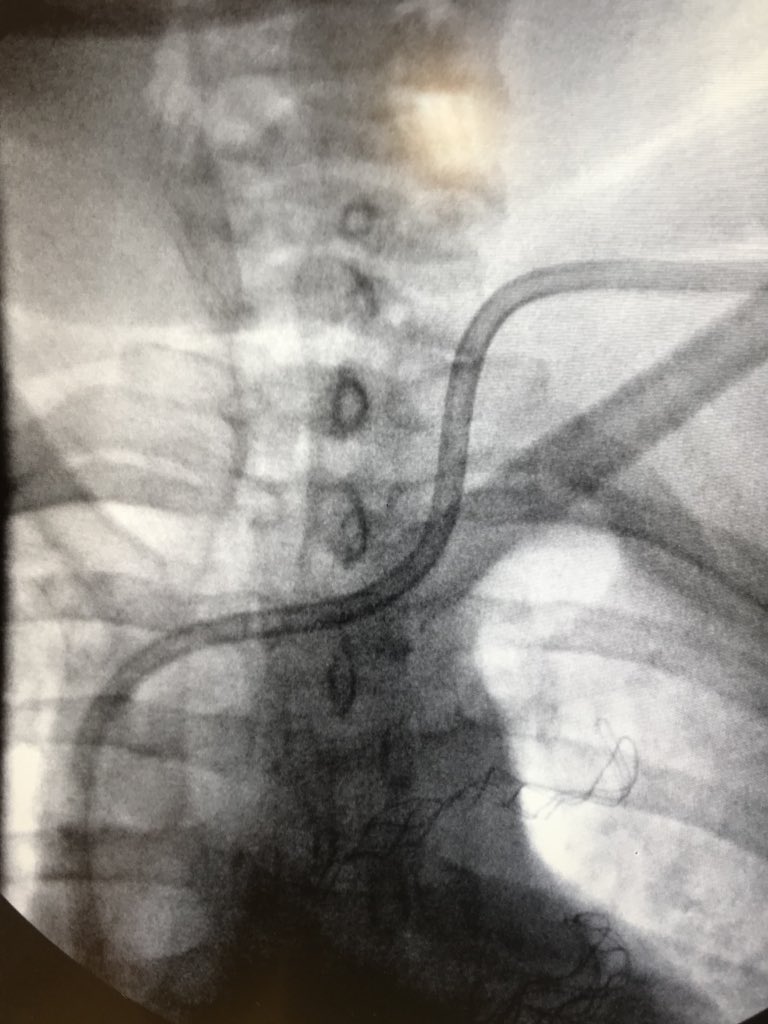

New study @AnnalsofIM bit.ly/2Km3KYu by @DrTalenfeld @WeillCornell: Percutaneous ablation for T1a #renalcancer has similar 5-year survival rates to radical nephrectomy but with far fewer 30-day complications and less #kidneyfailure.